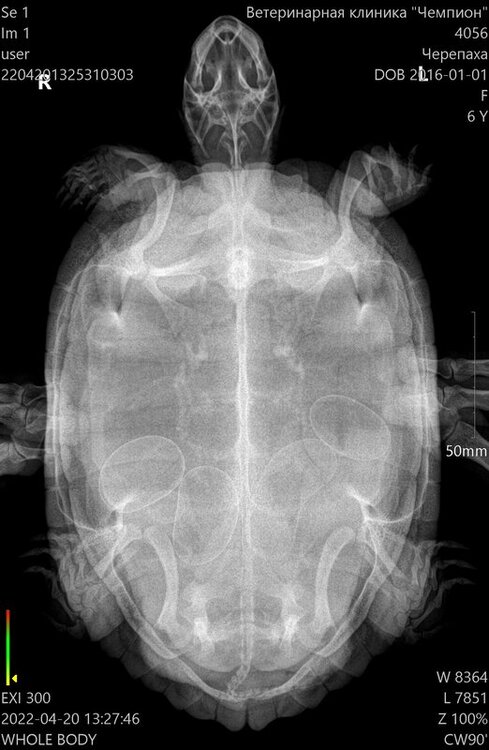

ольшади Ваше имя: Мила Локация: Череповец Опубликовано: 21 апреля 2022 Опубликовано: 21 апреля 2022 Добрый день! В нашем городе нет герпетолога, поэтому просим Вашей консультации. Три года у нас живут две крсноухие черепахи-девочки (отданы были взрослыми, со слов владельцев им было по три года). Последние две недели одна из черепаз перестала принимать пищу, ведет как никогда раньше, а именно мечется по аквариуму и на островке роет задними лапами. Прочитала в интернете, что такое поведение вызвано беременностью. Сделали рентген, действительно яйца есть ( пять штук). Мой вопрост такой:все ли в порядке с яйцами и черепахой, так как уже две недели она пытается и не может их отложить?

ольшади Ваше имя: Мила Локация: Череповец Опубликовано: 23 апреля 2022 Автор Опубликовано: 23 апреля 2022 Добрый день! Спасибо за ответ), тоесть судя по рентгену ей уже пора нестись? вес 1,3кг

Консультанты moth Ваше имя: Мария Локация: Москва Опубликовано: 23 апреля 2022 Консультанты Опубликовано: 23 апреля 2022 @ольшади учитывая рентген и поведение - да, пора